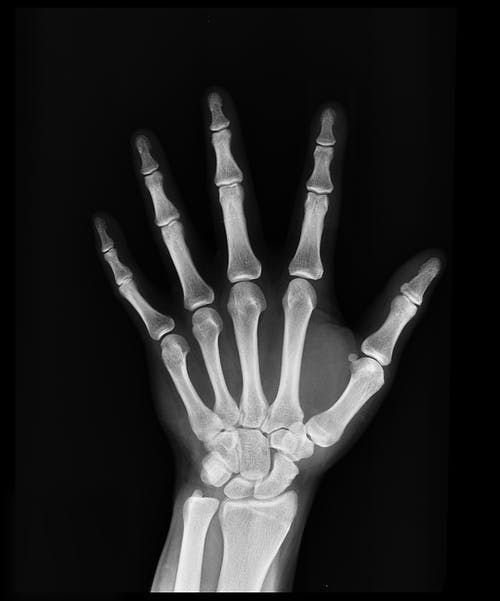

| An interesting paradigm: How can a woman have soft bones and kidney stones at the same time? The bones are the biggest depository for calcium in the body. Women with osteoporosis can lose calcium from their bones and have it be deposited in her kidneys. From there it is flushed out as hard, jagged crystals that are excruciatingly painful to pass. Bones are actually made from 17 essential nutrients including magnesium which is the most important mineral along with calcium.